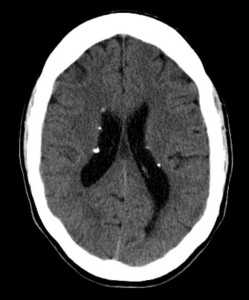

КТ головного мозга при туберозном склерозе. Видны кальцинированные субэпендимальные узелки в стенках боковых желудочков.

Диагностировать туберозный склероз возможно лишь совместными усилиями нескольких специалистов (невролога, офтальмолога, дерматолога, кардиолога, нефролога) с проведением широкого аппаратного обследования пациента. Церебральная эпилептическая активность регистрируется при помощи ЭЭГ и ЭЭГ с пробами. У детей до года возможно проведение нейросонографии. Наибольшую значимость в диагностике поражений ЦНС имеют КТ и МРТ. КТ головного мозга более информативно в отношении кальцифицированных туберов и субэпендимальных узлов, а МРТ головного мозга — в выявлении некальцифицированных туберов. С целью своевременной диагностики астроцитомы детям, имеющим туберозный склероз, рекомендовано прохождение МРТ или КТ-исследования не реже чем раз в 2 года.

Туберозный склероз на изображениях визуализируются обызвествленные узлы или кальцифицированные субэпендимальные гамартомы.

о Кальцифицированные субэпендимальные узлы (гамартомы)

- В 98% случаев-субэпендимальные узлы (СЭУ)

2. КТ при туберозном склерозе:

• Бесконтрастная КТ:

о СЭУ:

- Вдолькаудоталамической вырезки > предсердия» височной

- 50% Са (прогрессирующее в течение одного года)